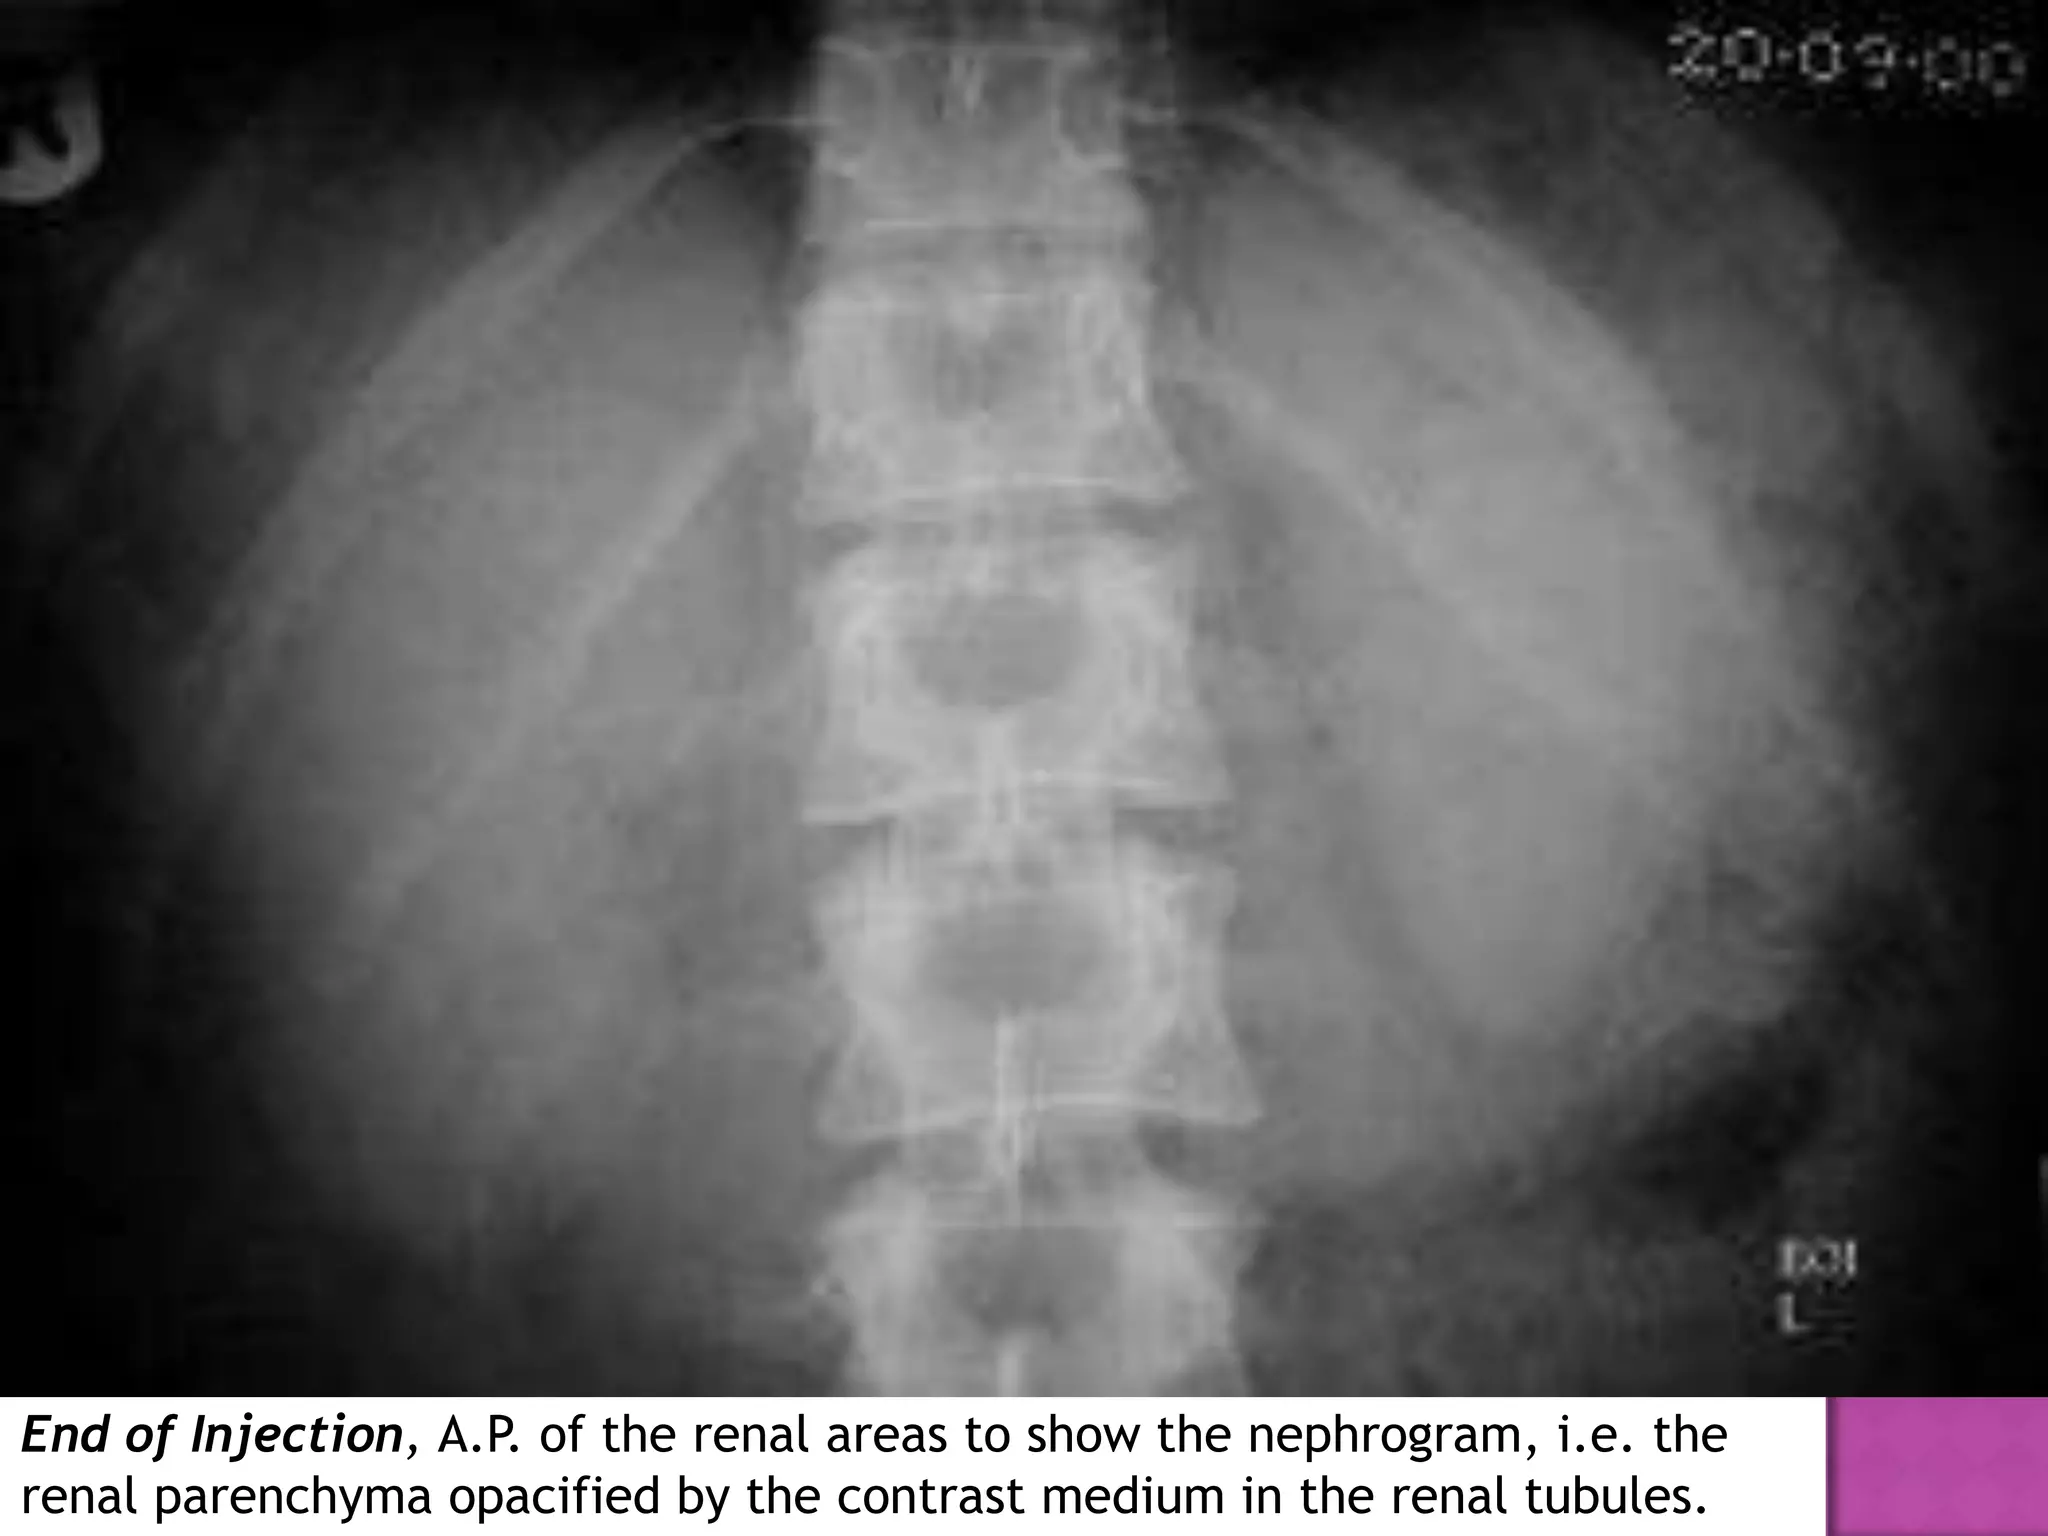

End of Injection, A.P. of the renal areas to show the nephrogram, i.e. the

renal parenchyma opacified by the contrast medium in the renal tubules.

End of Injection,A.P. of the renal areas to show the nephrogram, i.e. the renal parenchyma opacified by the contrast medium in the renal tubules.